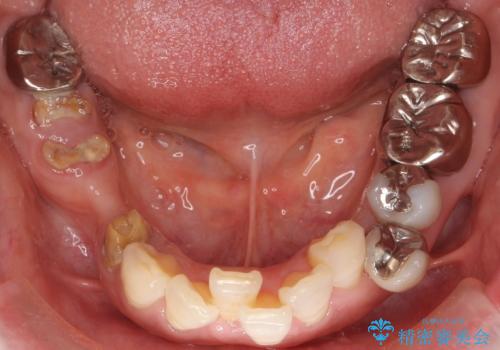

- 虫歯と歯並びを治したいとご希望された患者様です。

精査したところ、左下の小臼歯(左下5)の銀の詰め物の下に大きなう蝕を認めました。

またその手前の歯(左下4)は頬側転位していることを気にされておりました。

矯正をおすすめしましたが希望されず、最小限の方法で虫歯と歯並びを治したいとのことでした。

患者様のご希望により、セラミッククラウンにより可及的にう蝕除去後の補綴及び歯並びの改善を行いました。